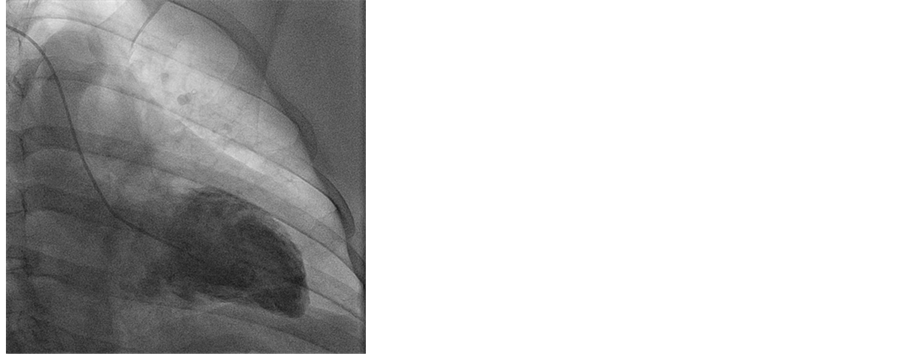

A 55-year-old woman presented early in the morning with a past history of hypothyroidism and diabetes mellitus accompanied by her husband to the emergency department after a sudden onset substernal chest pressure radiating to the shoulder blades and shortness of breath. An electrocardiogram and cardiac enzymes suggested acute myocardial infarction. Coronary angiography was performed which showed minimal coronary artery disease without a hemodynamically significant stenosis. Left ventriculography was notable for a low normal ejection fraction of 35%, an akinetic anterior and hypokinetic mid-ventricular walls (Figure 1). These findings were consistent with mid-ventricular ballooning syndrome.

Figure 1. Left angiography showing akinetic anterior and hypokinetic mid-venticular walls confirming midventricular ballooning syndrome.